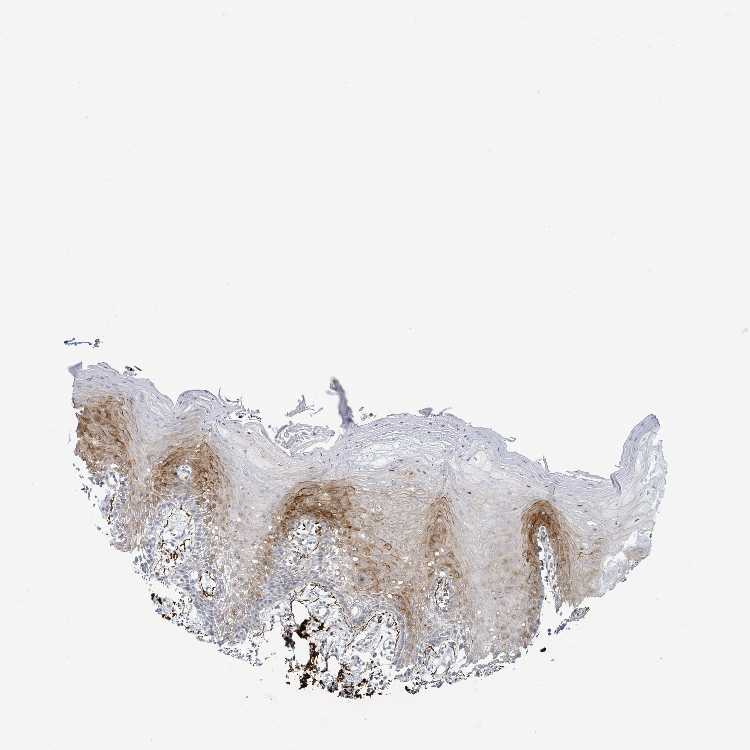

TISSUE PRIMARY DATA ORAL MUCOSA Show tissue menu

ORAL MUCOSA - Antibody stainingi

Antibody staining in the annotated cell types in the current human tissue is reported as not detected, low, medium, or high, based on conventional immunohistochemistry profiling in selected tissues. This score is based on the combination of the staining intensity and fraction of stained cells.

Each image is clickable and will lead to virtual microscopy that enables deeper exploration of all samples and also displays staining intensity scores, fraction scores and subcellular localization as well as patient and tissue information for each sample.

Antibody HPA050920

Squamous epithelial cells Medium